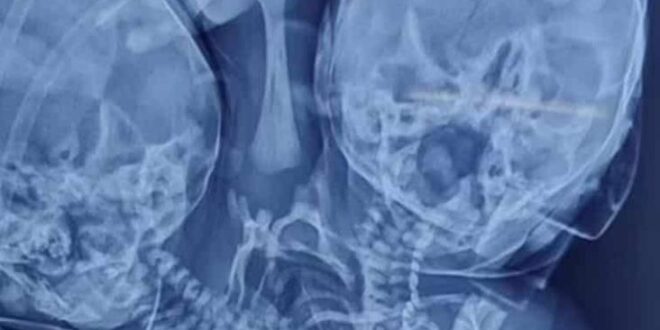

El nacimiento de un bebé le ha dado la vuelta al mundo después de nacer con dos cabezas, tres manos y dos corazones a causa de una extraña condición médica.

Una mujer de la India, Shaheen Khan, que en un principio esperaba creía estar embarazada de un par de gemelos de acuerdo a una ecografía, dio a luz a un bebé que nació con dos cabezas, tres manos y dos corazones, todo unido por un solo torso, una extraña afección denominada parapagus dicefálico

El problema presentado se produce en el útero de la madre y con normalidad se considera mortal, por lo que suele provocar el nacimiento de un niño muerto, aunque este no fue el caso. Sin embargo, los médicos han asegurado que no tienen considerarlo operarlo pese a que sobrevivió los primeros días.

El periódico The Sun ha reportado que, por el momento, no está claro si este nacimiento está siendo considerado como de gemelos unidos o como un solo niño Información Noticieros Televisa